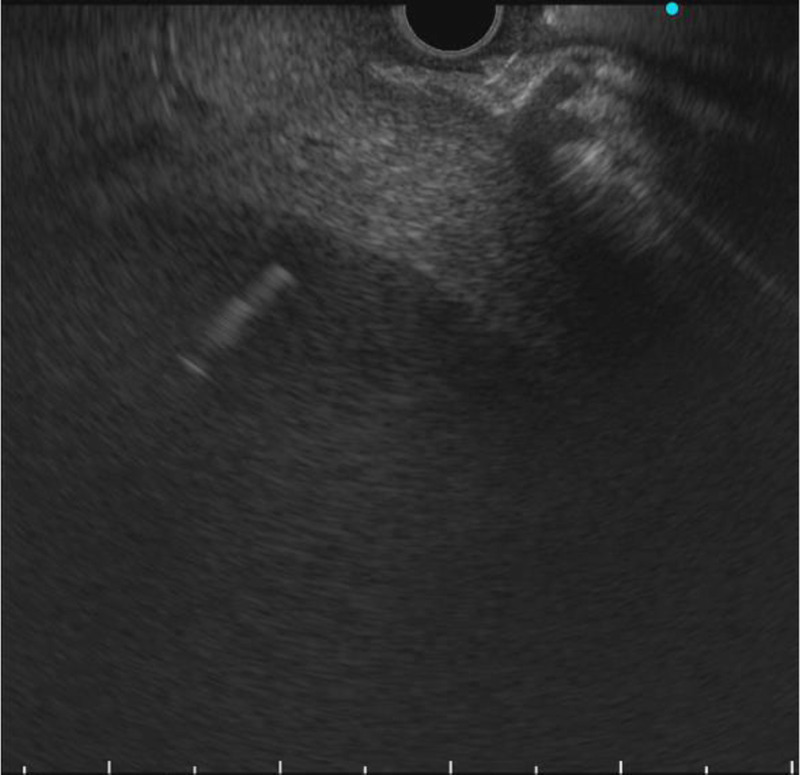

EUS-guided abscess drainage in an elderly patient with an abscess in the right liver lobe (with video).

一名右肝叶脓肿的老年患者在 EUS 引导下进行脓肿引流(附视频)。